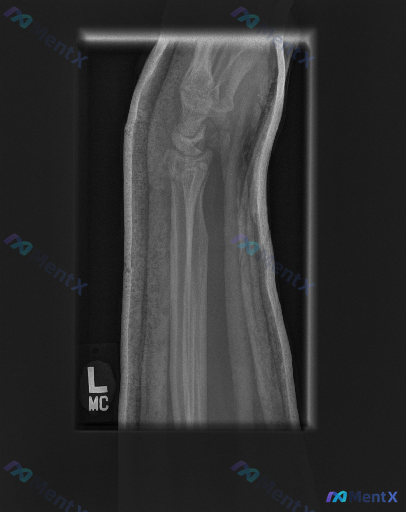

整理到一份左前臂及腕部侧位X光片的影像资料,先和大家同步客观所见的线索: 1. 骨骼方面:桡骨远端背侧和掌侧皮质有连续性中断,可见骨折线涉及关节面,断端有背侧移位、背侧成角的表现,局部有粉碎或压缩改变;尺骨远端(尺骨茎突)处也可见透亮线。 2. 关节方面:桡腕关节的对应关系有改变,随桡骨移位出现背侧...